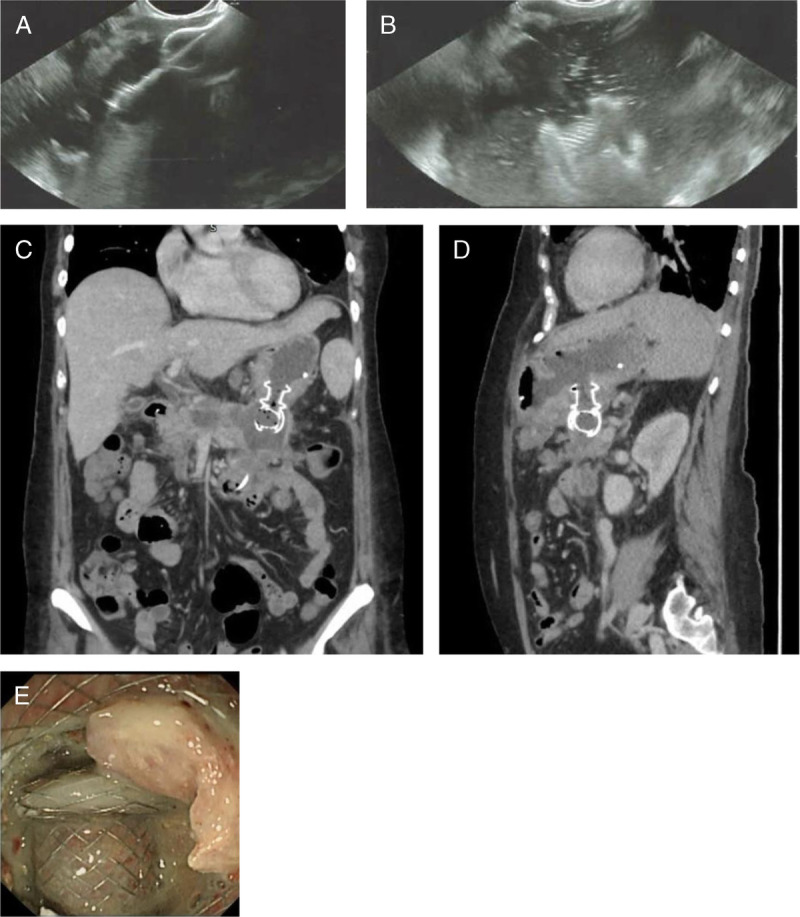

eus引导的介入治疗已成为广泛接受的胰周积液引流的治疗管理选择。除了内窥镜技术外,EUS介入还需要了解内窥镜支架置入技术并熟悉可用的支架和部署系统。虽然通常安全有效,但即使在专家手中,也可能发生正确支架定位的技术故障或严重的不良事件。在这篇文章中,我们讨论了跨壁eus引导支架置入中常见和罕见的不良事件,预防它们的方法,以及发生时的管理选择。了解可能出错的风险,结合临床专业知识、高水平的技术技能和充分的培训,可以确保eus引导引流手术的安全进行。与患者讨论手术风险及其可能性是同意过程的基本部分。

EUS-guided interventions have become widely accepted therapeutic management options for drainage of peripancreatic fluid collections. Apart from endosonographic skills, EUS interventions require knowledge of the endoscopic stenting techniques and familiarity with the available stents and deployment systems. Although generally safe and effective, technical failure of correct stent positioning or serious adverse events can occur, even in experts' hands. In this article, we address common and rare adverse events in transmural EUS-guided stenting, ways to prevent them, and management options when they occur. Knowing the risks of what can go wrong combined with clinical expertise, high levels of technical skills, and adequate training allows for the safe performance of EUS-guided drainage procedures. Discussing the procedural risks and their likelihood with the patient is a fundamental part of the consenting process.